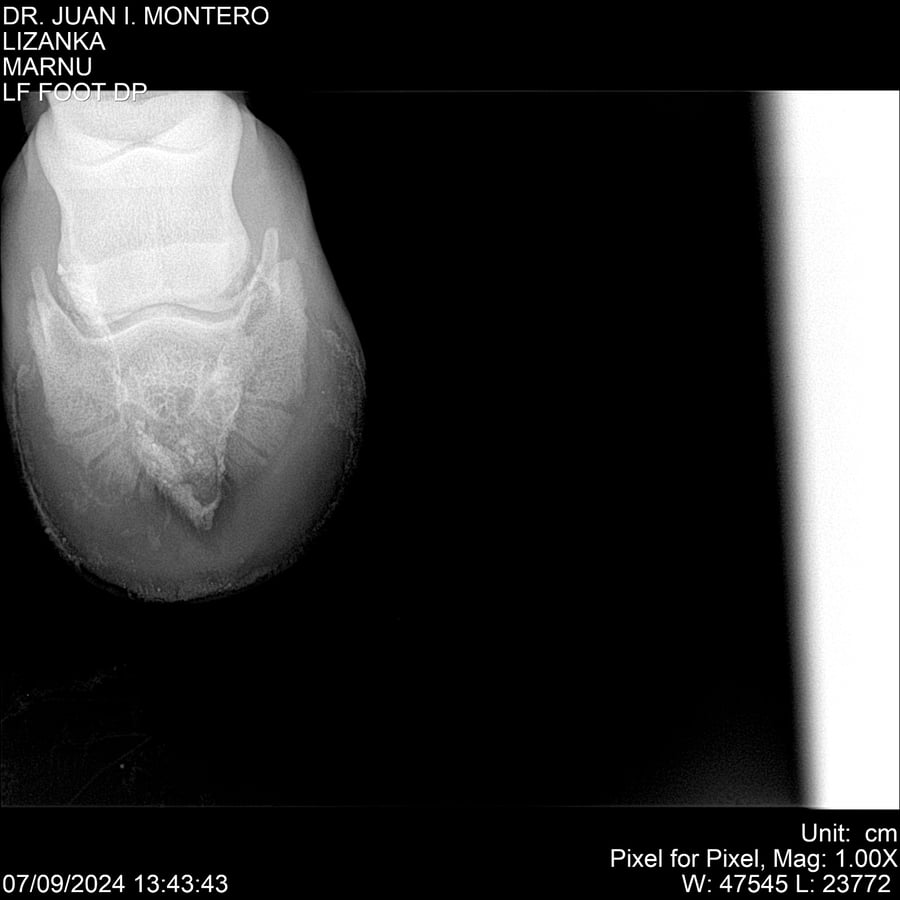

LOTE 18, LIZANKA Lote Anterior Volver al remate Lote Siguiente Ficha Contacto Montevideo - Ficha del Lote Identificador: #282512 Categoría: Yeguarizos Montevideo - 62 Visualizaciones ClicData Contacto Empresa: Abelenda N. R., Walter Hugo Nombre*: Teléfono* : E-mail* : Mensaje Enviar Registrese gratis Este contenido Exclusivo está disponible sólo para usuarios registrados Ingresar